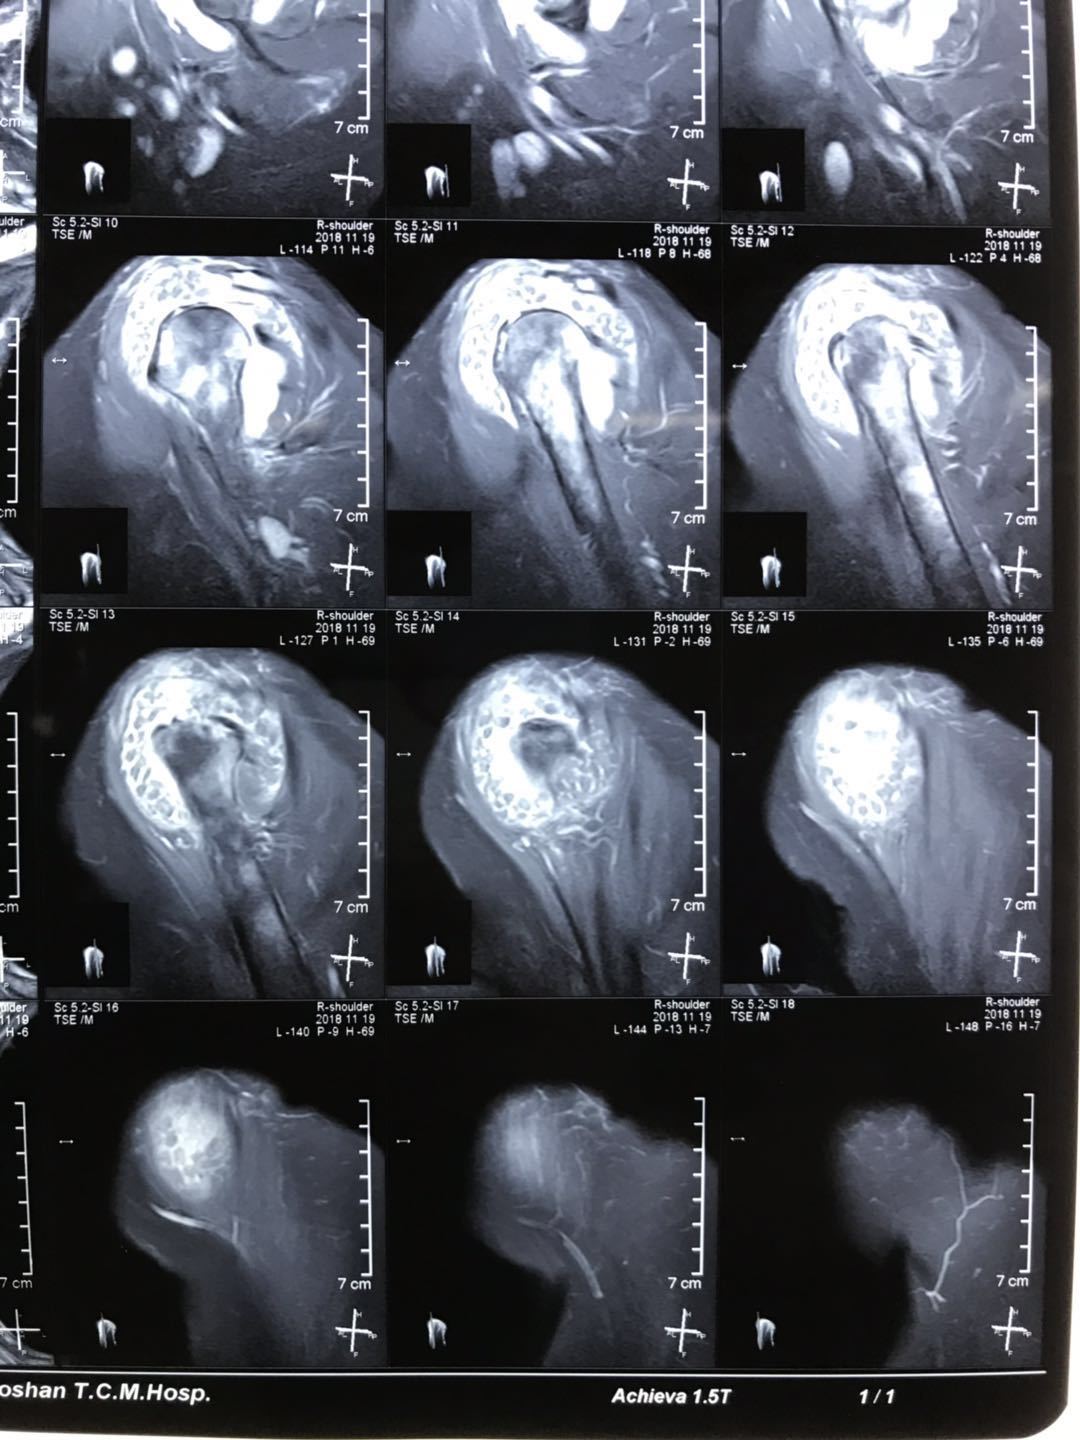

严重的肩关节 滑膜软骨瘤病 一例 - 好大夫在线

图片尺寸1080x1440